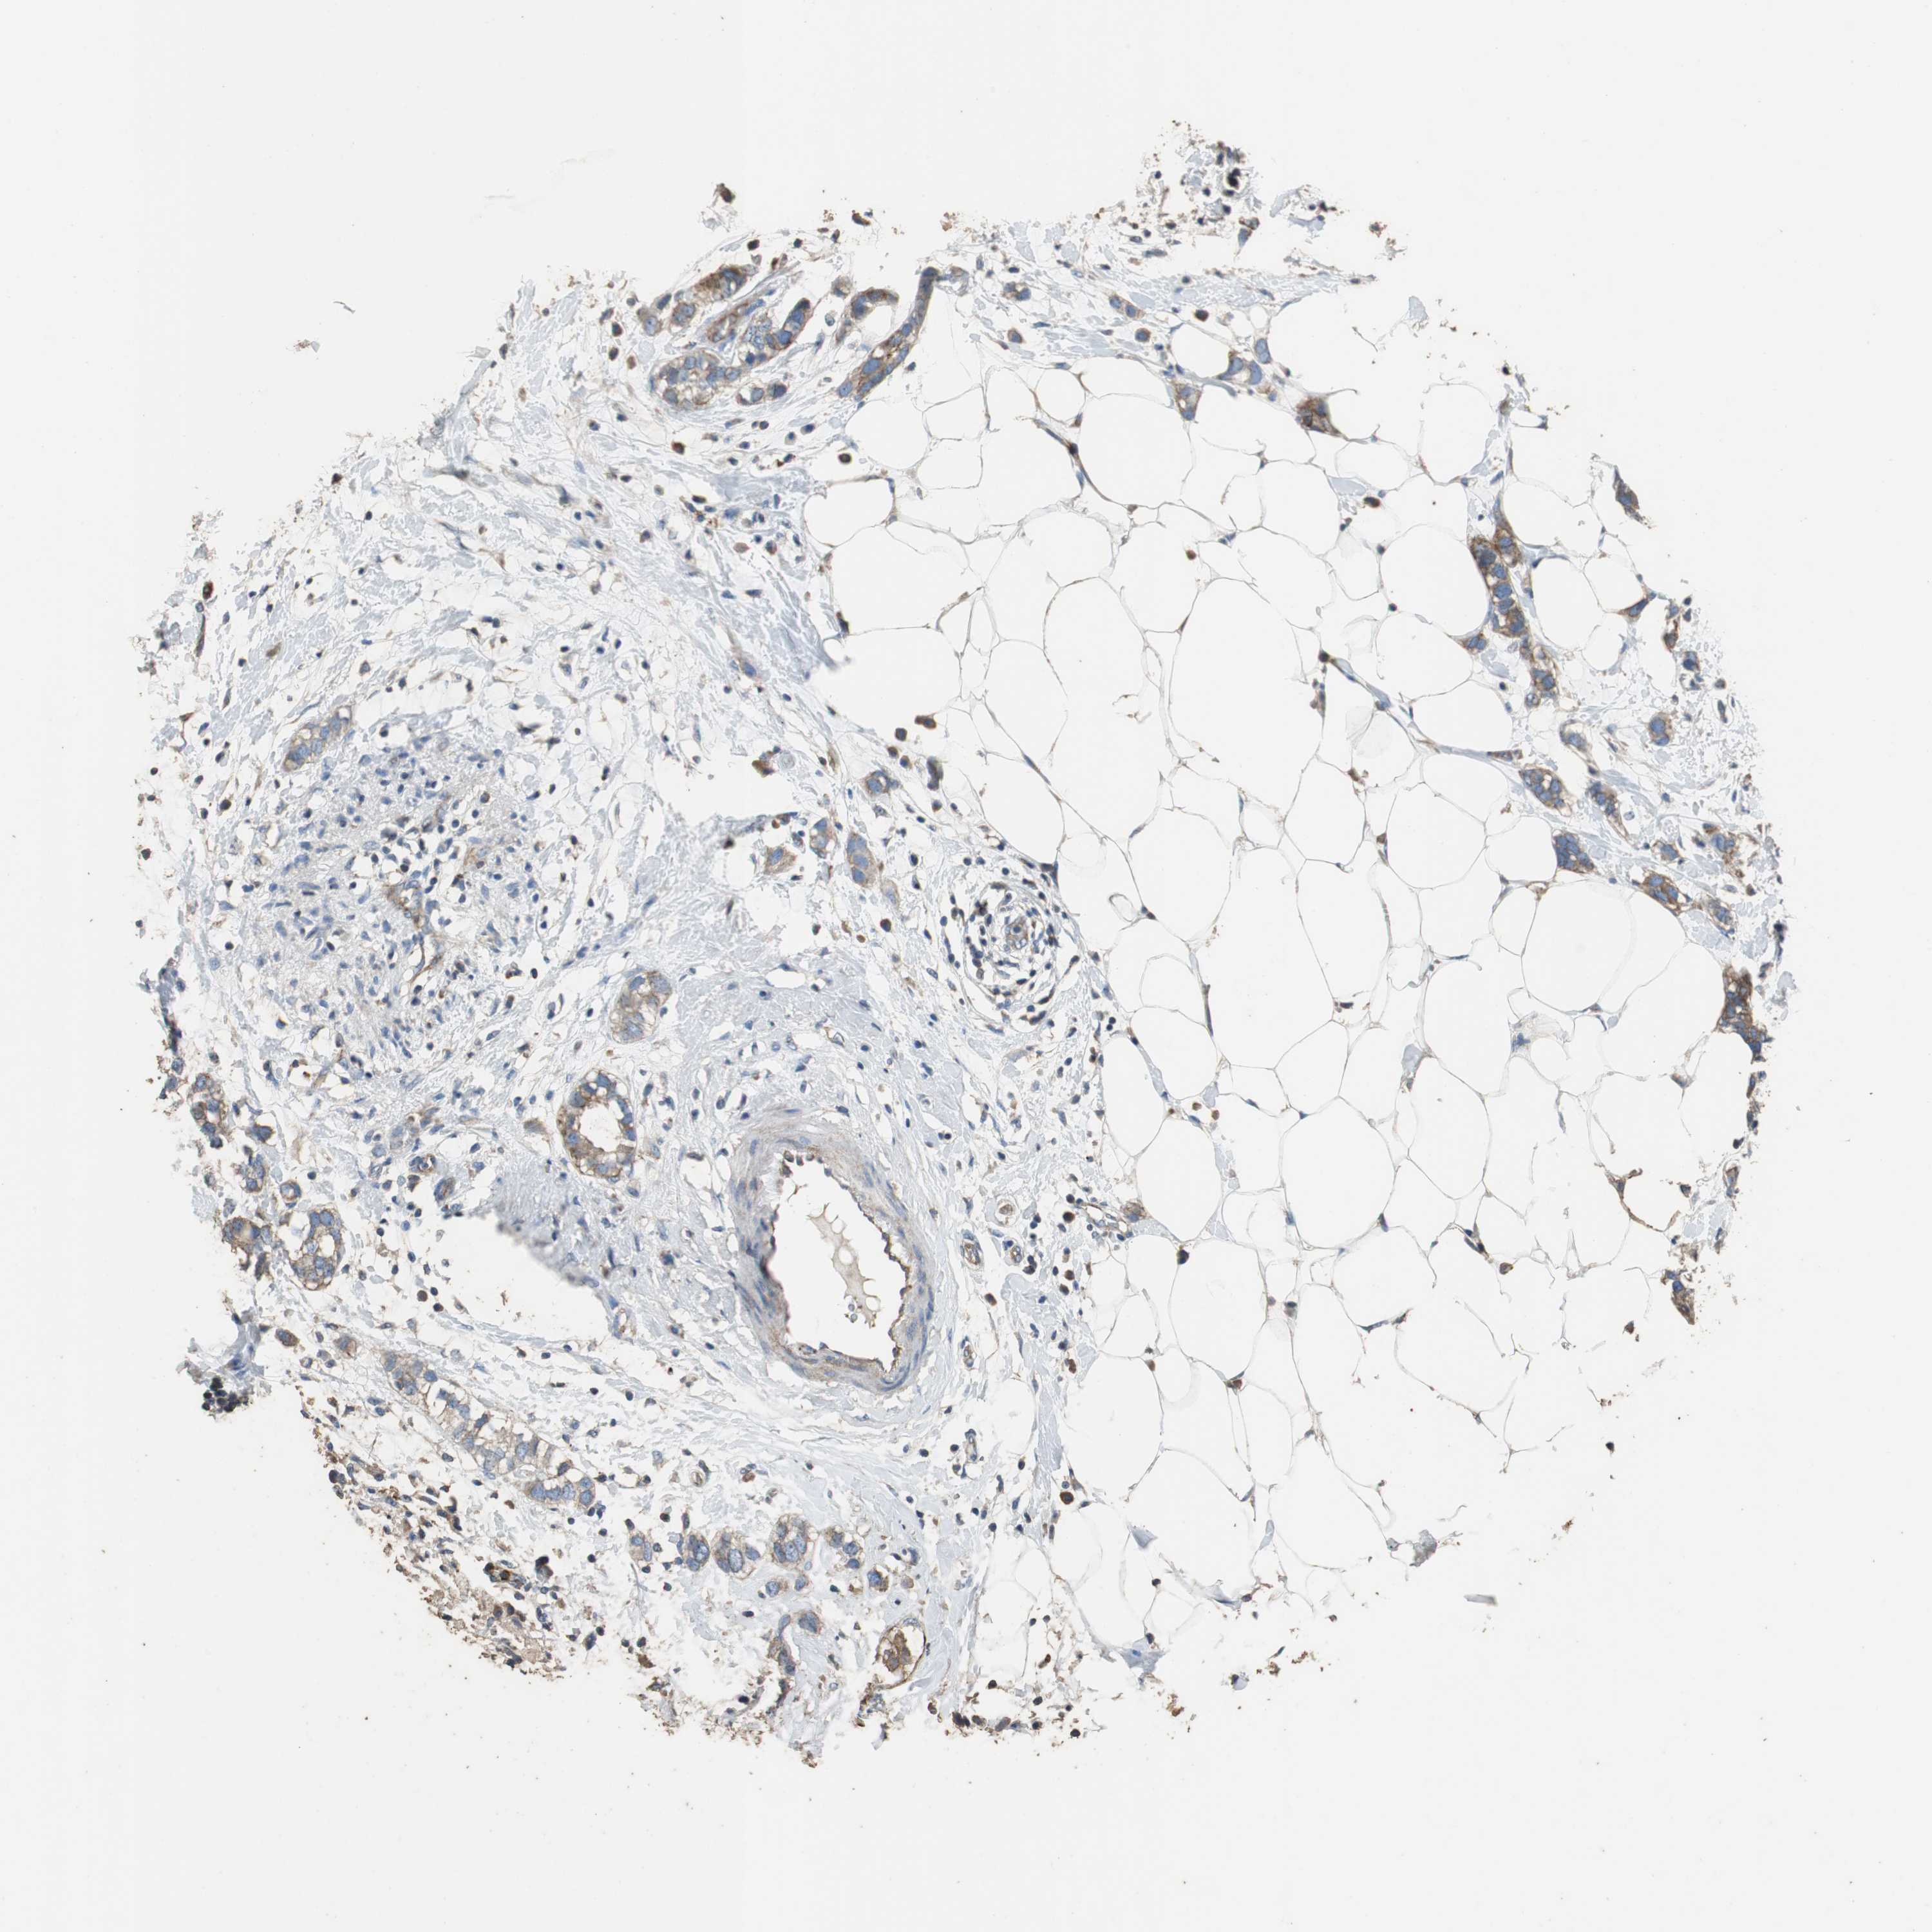

BRCA TCGA BRCA VALIDATION PROTEIN EXPRESSION